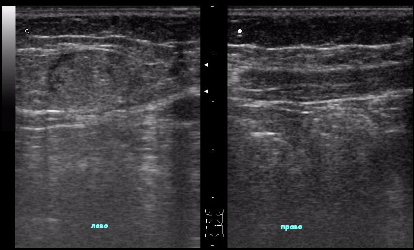

УЗИ мягких тканей

Ультразвуковое исследование мягких тканей проводится с целью диагностики липом, гематом, грыж, отеков, травм, уплотнений, а также установления причин мышечных болей. Обследование мягких тканей позволяет определить размеры новообразований, характер новообразований и кровотока в области опухоли методом допплерографии.

Это наиболее безопасный и эффективный способ, который можно осуществлять многократно в течение короткого промежутка времени, что крайне удобно при диагностике подозрительных новообразований на ранних стадиях развития, а также контроле над их лечением.